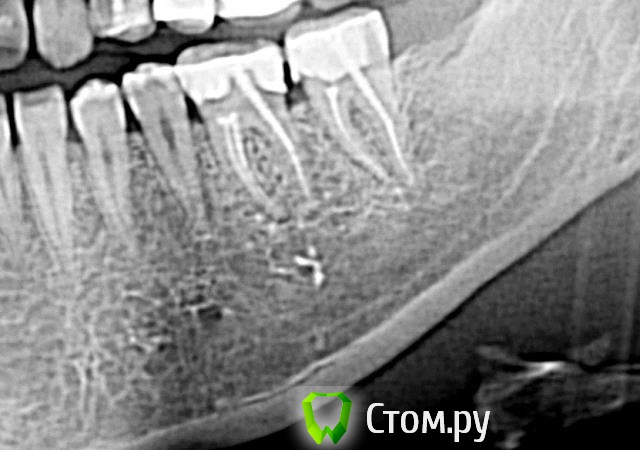

Фини7 Опубликовано 13 ноября, 2013 Поделиться Опубликовано 13 ноября, 2013 (изменено) Здравствуйте! После чистки кармана прошло 6 дней (между 6 и 7 зубом слева, нижняя челюсть). До сих приходится периодически пить обезболивающие, т.к. ноющая боль не проходит. Само место надреза воспаленное. Лечение: пока полощу хлоргексидином. Через некоторое время буду делать коронки на эти два зуба.Врач в отпуске, решила обратиться к вам. Пожалуйста, подскажите, является ли нормой такой срок для болезненных ощущений? На всякий случай прикладываю снимок. Изменено 13 ноября, 2013 пользователем Фини7 Ссылка на комментарий

IvanK Опубликовано 13 ноября, 2013 Поделиться Опубликовано 13 ноября, 2013 Здравствуйте. У Вас на зубах нависающие края пломб и на 6 и на 7. Обратитесь к Ортопеду. Зубы нуждаются в протезировании. 3 Ссылка на комментарий

Bier Опубликовано 13 ноября, 2013 Поделиться Опубликовано 13 ноября, 2013 +1 пока не поменяют пломбы (в идеале на коронки), ничего там не пройдет. Но перед этим еще каналы перелечить нужно 1 Ссылка на комментарий